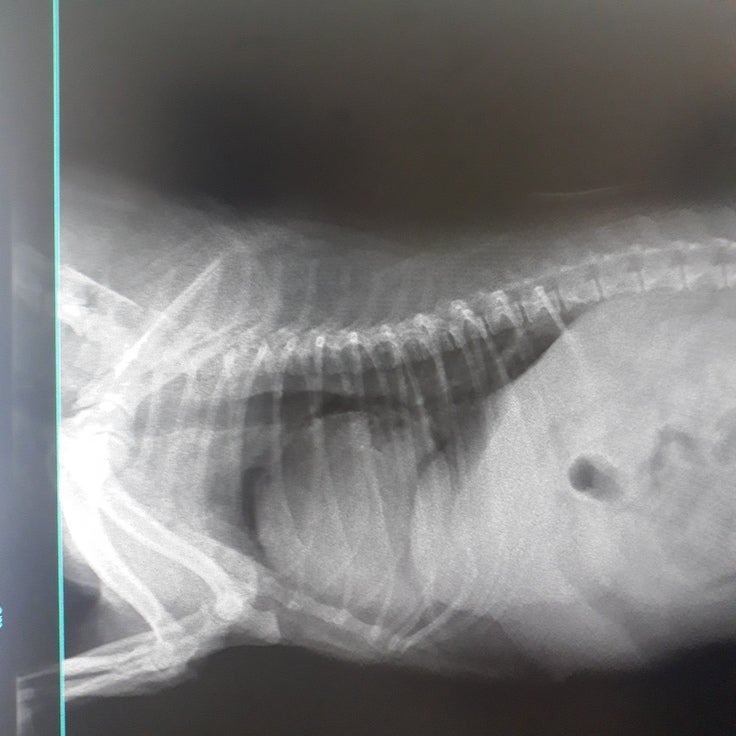

電話を切ってすぐに獣医師のところへ。B院で撮ったレントゲン、検査結果を元に

麻酔中に亡くなる可能性もあるし、合併症の可能性もある。でも助かる可能性もある。

本日、医院のお昼休みの時間帯に手術を行うという段取りでしたが、心臓の様子、呼吸の様子をみて、本日の夜の手術になりました。その間も、万が一がある・・・というご説明をいただき、助かる可能性があるのならということで承諾しました。21時過ぎ、(子宮摘出手術は無事に終わりました!)と、電話がありました。後日見せていただいたもの・・・・。苦手な方はスルーして下さい。

通常の子宮はボーペンサイズの太さだそうです。

2020/10/06 15:04このサイトを上手く使いこなせなく申し訳ありません。先日子宮摘出手術後の子宮になります。全くの無知だったのですが、通常の子宮はボールペンサイズの太さということで、ここまで晴れてしまっておりました。心臓弁膜症や膵炎を併発していた中、無事に手術を終えることが出来ました。 もっと見る